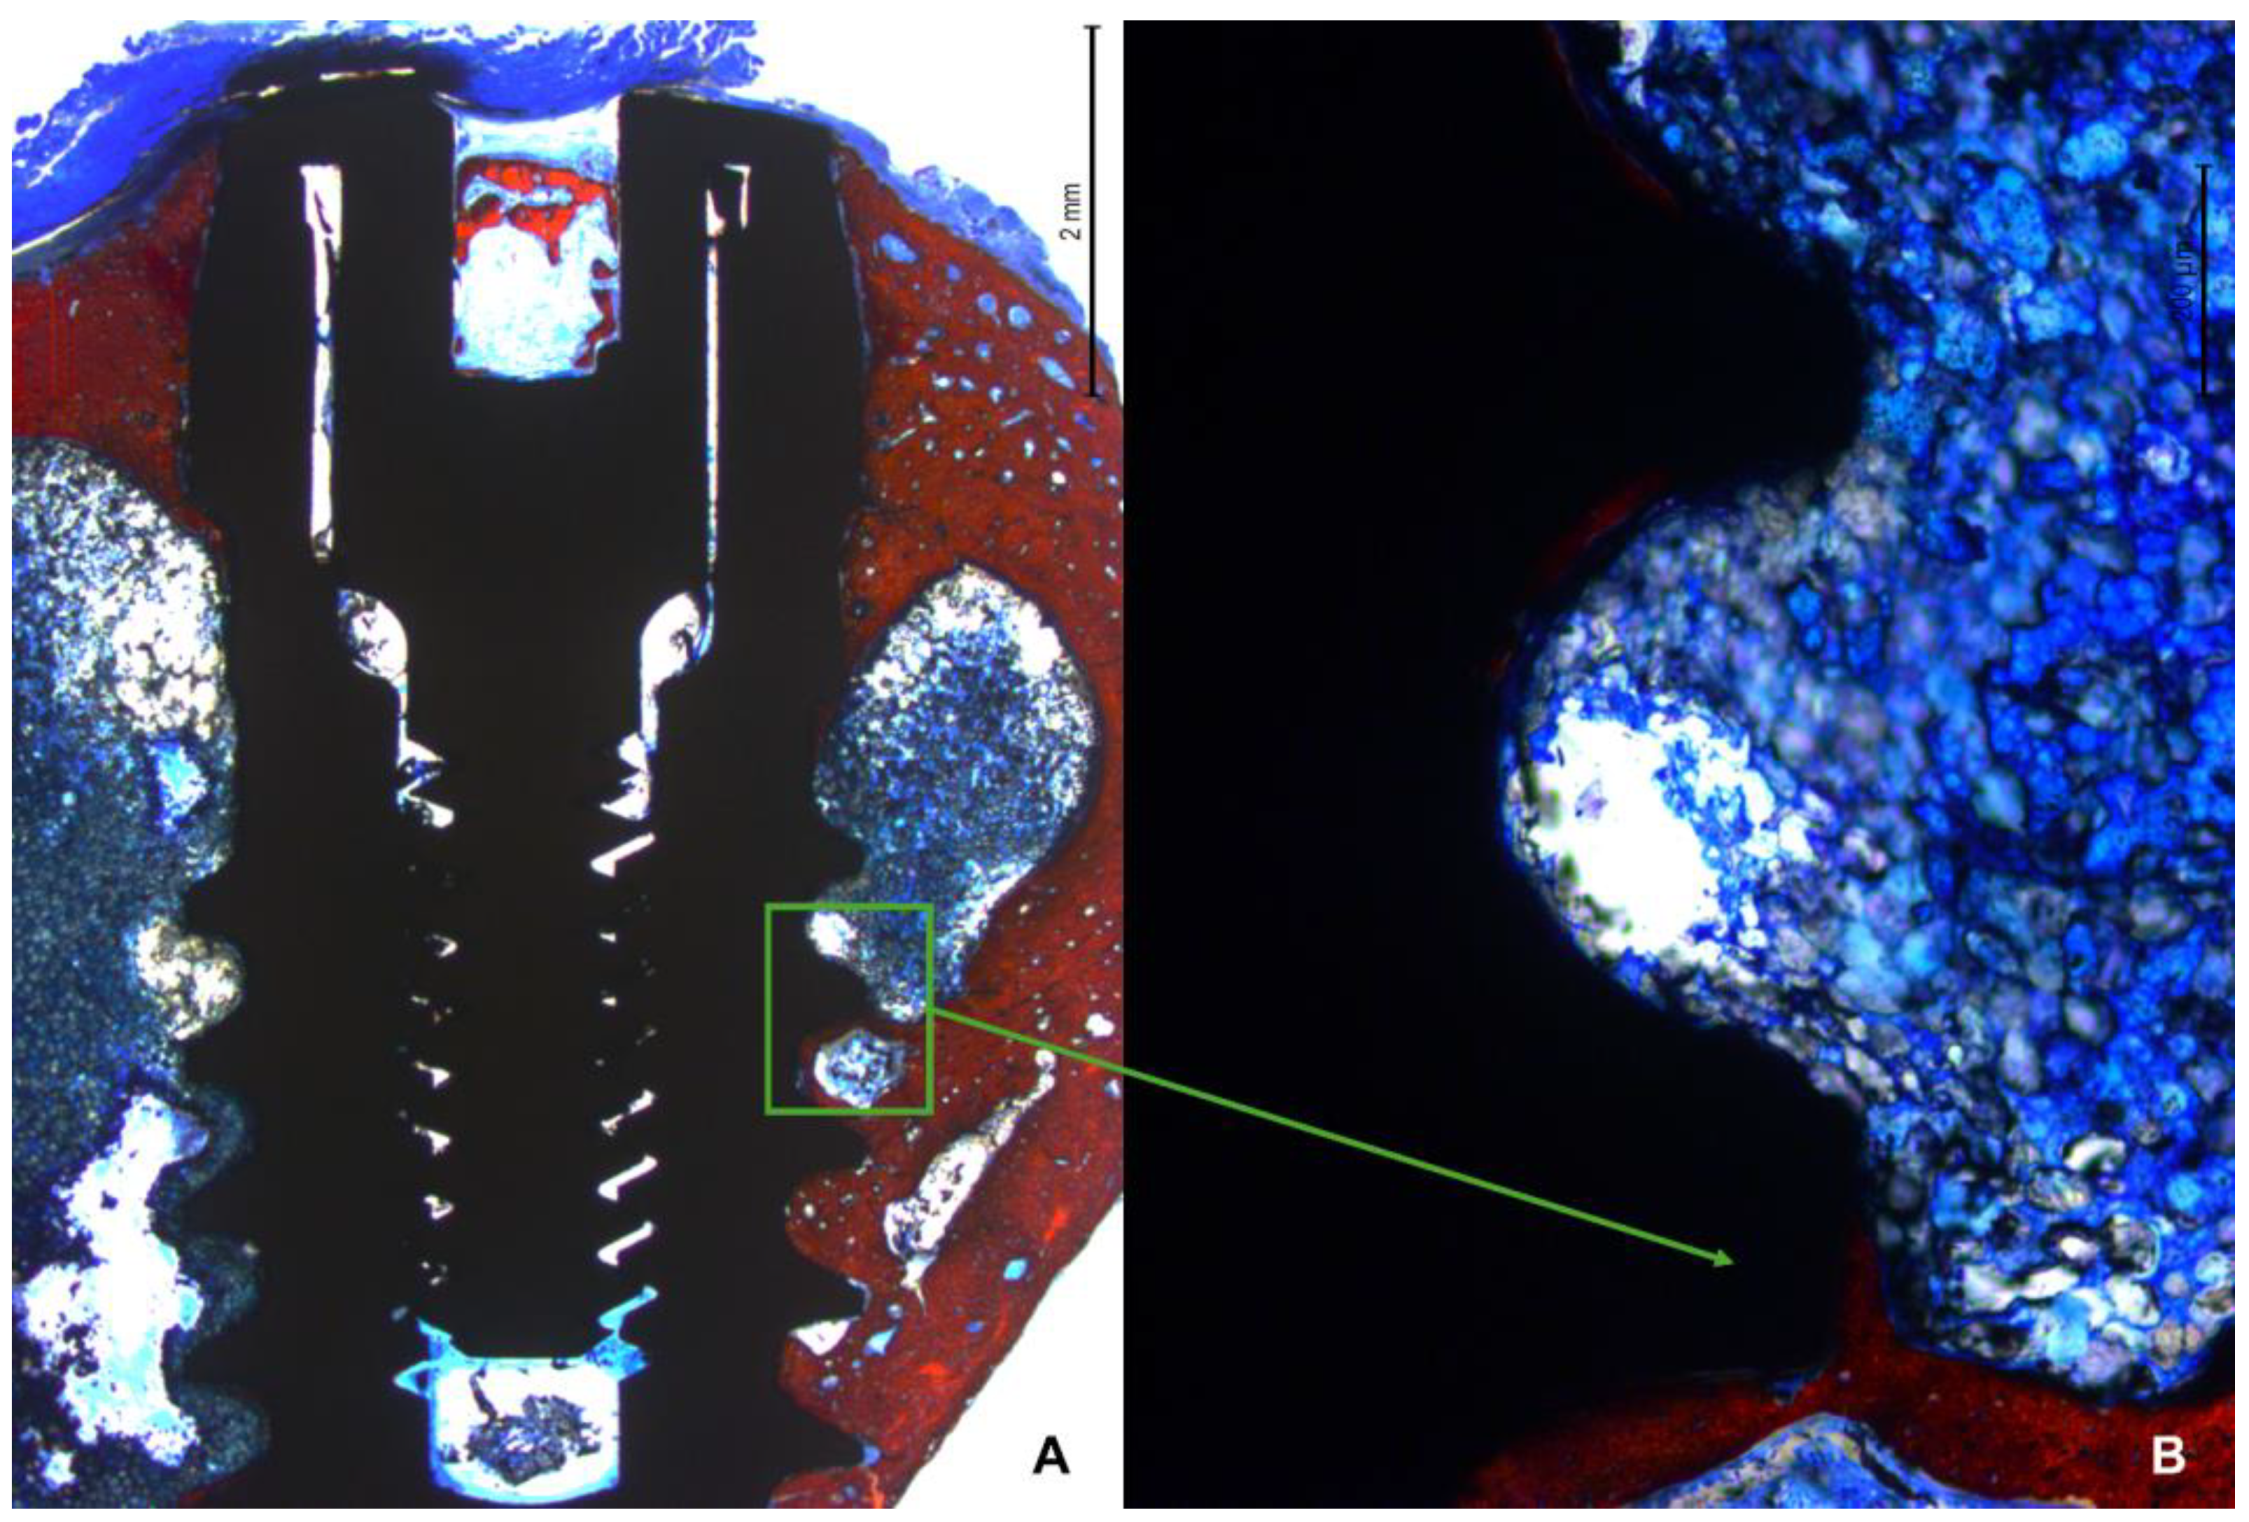

In the apical region, several implants breached the cortical layer (Figure 7 A,B). Nevertheless, new bone formation in this region completely closed the osteotomy, effectively isolating the internal environment of the tibia from the external.

Figure 7. Photomicrograph under 16x magnification of the implant apical region. A: Implant apical area with apex perfectly inserted at the cortical layer. B: Apical region of the implant surpassing the cortical layer, however complete closure of the region with new bone is observed.